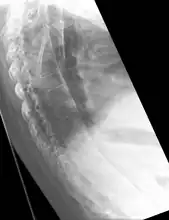

The earliest changes demonstrable by plain x–ray shows erosions and sclerosis in sacroiliac joints. Progression of the erosions leads to widening of the joint space and bony sclerosis. X-ray spine can reveal squaring of vertebrae with bony spur formation called syndesmophyte. This causes the bamboo spine appearance. A drawback of X-ray diagnosis is the signs and symptoms of AS have usually been established as long as 7–10 years prior to X-ray-evident changes occurring on a plain film X-ray, which means a delay of as long as 10 years before adequate therapies can be introduced.[19]

Lateral X-ray of the mid back in ankylosing spondylitis

X-ray showing bamboo spine in a person with ankylosing spondylitis